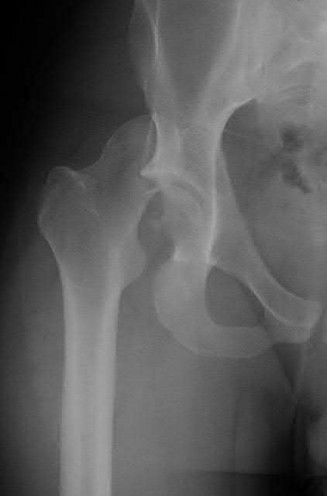

Question 1:

A 12-year-old obese boy presents with vague left thigh and knee pain. He is diagnosed with a Slipped Capital Femoral Epiphysis (SCFE) as seen in similar clinical scenarios. During percutaneous in-situ fixation, unrecognized penetration of the guide wire into the hip joint occurs. What is the most likely specific complication resulting from this technical error?

Correct Answer: Chondrolysis

Explanation:

Chondrolysis is a severe complication of SCFE characterized by rapid destruction of the articular cartilage. While it can occur idiopathically, its most established iatrogenic cause is unrecognized intra-articular hardware penetration. The 'approach-withdraw' fluoroscopic technique is required during pinning to assure pins are entirely intraosseous. Avascular necrosis (AVN) is usually due to damage to the epiphyseal blood supply (retinacular vessels) secondary to the initial displacement, forceful closed reduction, or posterosuperior pin placement.